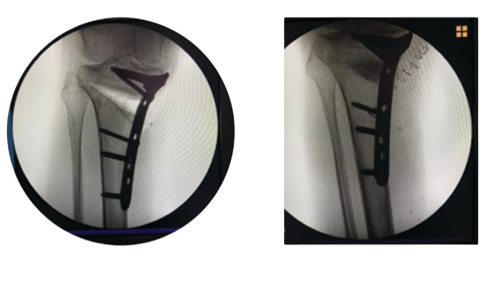

Open-wedge high tibial osteotomy (OWHTO) is a very common surgical technique for the treatment of knees with varus malalignment. Correcting the lower limb axis creates a gap on the tibia which can be filled with nanocrystalline hydroxyapatite (BoneSurg HA) to give an optimum support. Healing of that part is an important issue, since its delay or nonunion may result in loss of correction.

Resorbable bone replacements are formed by the rapid growth of bone tissue. Nanohydroxyapatite (nHA) has been shown to hasten bone remodelling and development, enabling the patient to resume full weight bearing sooner following OWHTO. Autologous iliac crest has long been considered the gold standard for bone grafting due to its high union rate, structural qualities, and potential for osteoconductive and osteoinductive growth. Furthermore, it is generally known that hydroxyapatite, which makes up bone mineral, is shaped like a needle or a rod and that its crystals are incredibly small, with an average length of 50 nm. When BoneSurg HA was mixed with cancellous bones, osteoblast cell proliferation was enhanced, cell apoptosis was inhibited, and macrophage inflammation was reduced.